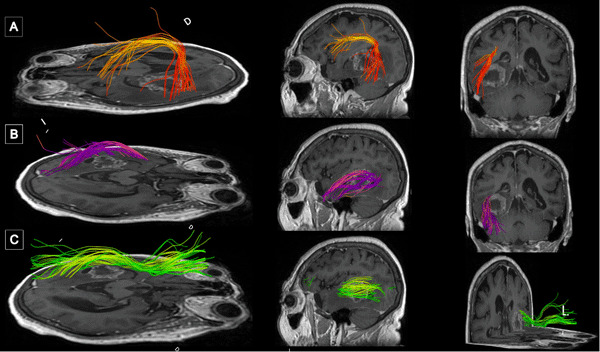

La resonancia magnética (RM) de encéfalo con gadolinio evidenció una lesión expansiva heterogénea, con áreas centrales de aspecto quístico y degeneración necrótica, localizada en la topografía temporomesial izquierda de aproximadamente 28 × 27 mm en plano axial y 29 × 26 mm en plano coronal, con realce heterogéneo tras la administración de contraste endovenoso. En secuencia de susceptibilidad magnética presentaba signos de restos de hemosiderina y/o microcalcificaciones. En el asta occipital y el atrio ipsilateral del ventrículo lateral, se evidenciaron formaciones quísticas con refuerzo periférico. La lesión descripta presentaba edema perilesional que comprometía el lóbulo temporal izquierdo y la región parietoccipital ipsilateral. Además, se observó dilatación del tercer ventrículo y ventrículo lateral homolateral. Las cisternas perimesencefálicas se encontraban libres, y las estructuras de la línea media, centradas. Las imágenes obtenidas eran sugestivas de una lesión de origen glial de alto grado (Figura 1). Se complementó con tractografía en la que se observó una disminución de la fracción de anisotropía a nivel del septum sagital con disrupción de las fibras de los tractos arcuato, frontooccipital inferior y longitudinal inferior izquierdo (Figura 2).

Figura 1. RM preoperatoria con contraste endovenoso. A y B) RM de encéfalo, cortes axial y sagital, respectivamente, en secuencia T1 contrastada, que evidencia lesión expansiva con realce heterogéneo localizada en topografía temporomesial izquierda. C) Corte axial en secuencia T2, se muestra heterogeneidad de la lesión con áreas centrales de aspecto quístico y degeneración necrótica. D) Corte axial en secuencia FLAIR que evidencia edema perilesional que compromete lóbulo temporal izquierdo y región parietooccipital ipsilateral.

Figura 2. Tractografía con reconstrucción 3D de los fascículos asociados. Disminución de la fracción de anisotropía a nivel del septum sagital con disrupción de las fibras de los tractos A) Arcuato izquierdo. B) Frontooccipital inferior izquierdo. C) Longitudinal inferior izquierdo.